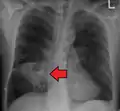

Lung abscesses are often on one side and single involving posterior segments of the upper lobes and the apical segments of the lower lobes as these areas are gravity dependent when lying down. Presence of air-fluid levels implies rupture into the bronchial tree or rarely growth of gas forming organism.

- Pulmonary abscess on CXR